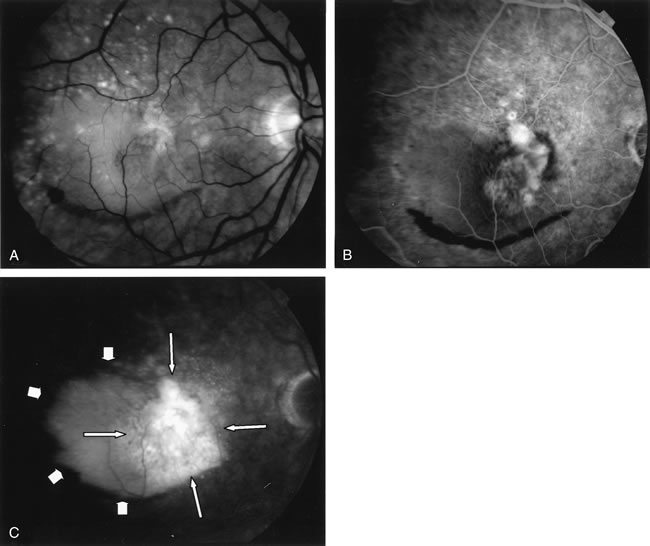

Fig. 7. Composite photograph of fluorescein angiography study in a patient with classic, subfoveal choroidal neovascularization (CNV) in the right eye. A The classic neovascular membrane appears as a well-defined area of hyperfluorescence in the early phases of the angiogram. There is leakage of dye from the classic net in the subretinal space throughout the study. B. In the late phase of the study, the edges of the CNV are fuzzy and indistinguishable.

Fig. 9. A. Clinical photograph of the left eye of a patient with exudative neurosensory macular detachment. There were also intraretinal and subretinal hard exudates, subretinal hemorrhage, and retinal pigment epithelium (RPE) changes. B–D. Fluorescein angiography of the same eye demonstrates the presence of stippled hyperfluorescence from the RPE, and late-phase oozing of dye of undefined origin. There was occult choroidal neovascularization.

Fig. 10. A. Red-free photograph of the right eye of a patient with wet age-related macular degeneration. There was a large, exudative pigment epithelium detachment (PED), with a narrow band of subretinal hemorrhage at its inferior border. A notch in the PED is present at its nasal edge. There were also soft drusen. B–C. Fluorescein angiography demonstrates pooling of dye into the PED (short arrows). There was also late hyperfluorescence of undefined origin consistent with occult choroidal neovascularization (long arrows). There was blockage of fluorescence at the inferior border of the PED caused by subretinal hemorrhage.

Fig. 11. A. Red-free photograph of the right eye of a patient with wet age-related macular degeneration reveals exudative, neurosensory detachment in the macula and a few subretinal hemorrhages. B. Early-phase fluorescein angiography demonstrates well-defined classic choroidal neovascularization (CNV) (arrowhead). C. Late-phase fluorescein angiography shows leakage of dye from the classic CNV surrounded by an area of late hyperfluorescence consistent with occult CNV (arrows).